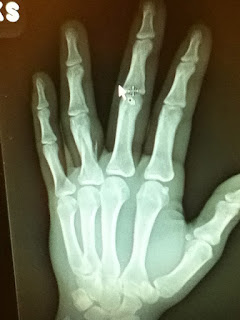

One time I broke my finger in a basketball game.